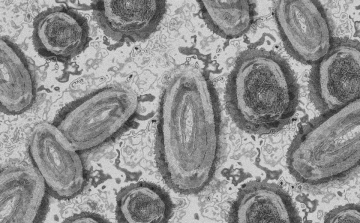

Meghaladta a 13 ezret a majomhimlő-fertőzöttek száma az Egyesült Államokban

Meghaladta a 13 ezret a majomhimlő-fertőzöttek száma az Egyesült Államokban, a legtöbb esetet Kaliforniában és New York államban regisztrálták.